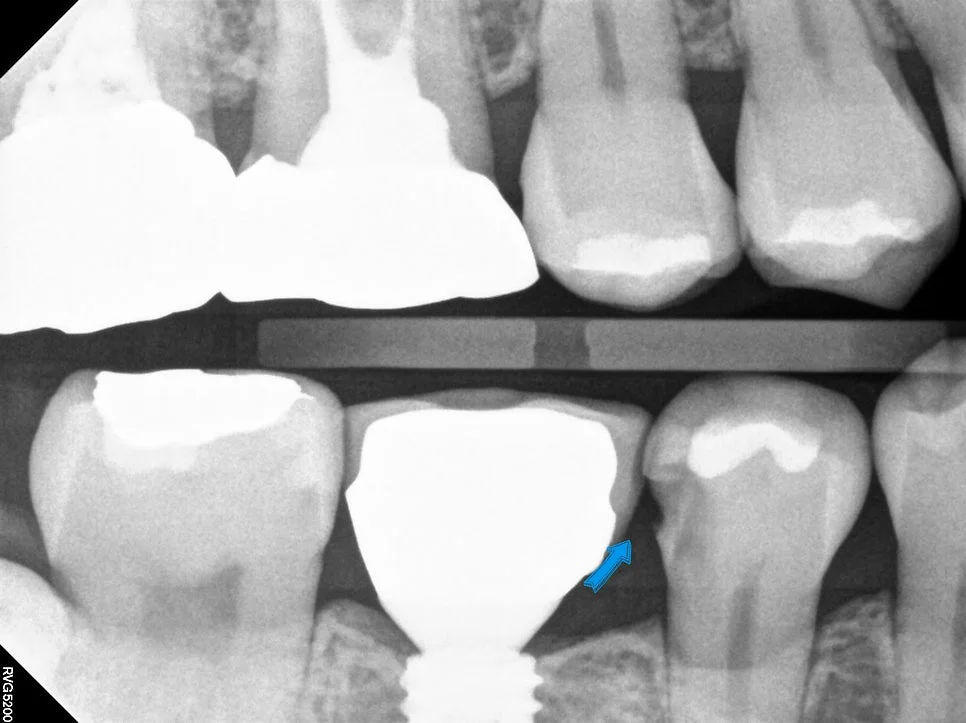

이렇게 틈이 벌어지면 음식물이 많이 끼게 되고 그 과정에서 충치가 생기는 경우가 흔한데요. 교익 방사선(Bitewing X-ray) 사진 촬영을 통해 치아 사이 충치를 확인해 보았는데요!

교익 방사선 사진 — 화살표로 치아 사이 충치(검은 음영) 위치 표시

방사선 사진상에서 치아가 있어야 할 위치에 검은 음영이 있다면 충치로 진단을 하는데 딱 그 자리에 충치가 있는 모습을 볼 수 있습니다ㅃ

해당 치아의 충치를 치료하고 음식물이 끼지 않게 하기 위해 임플란트와 긴밀한 틈(빡빡하게)을 만들어 주는 ‘인레이’ 치료를 계획합니다!